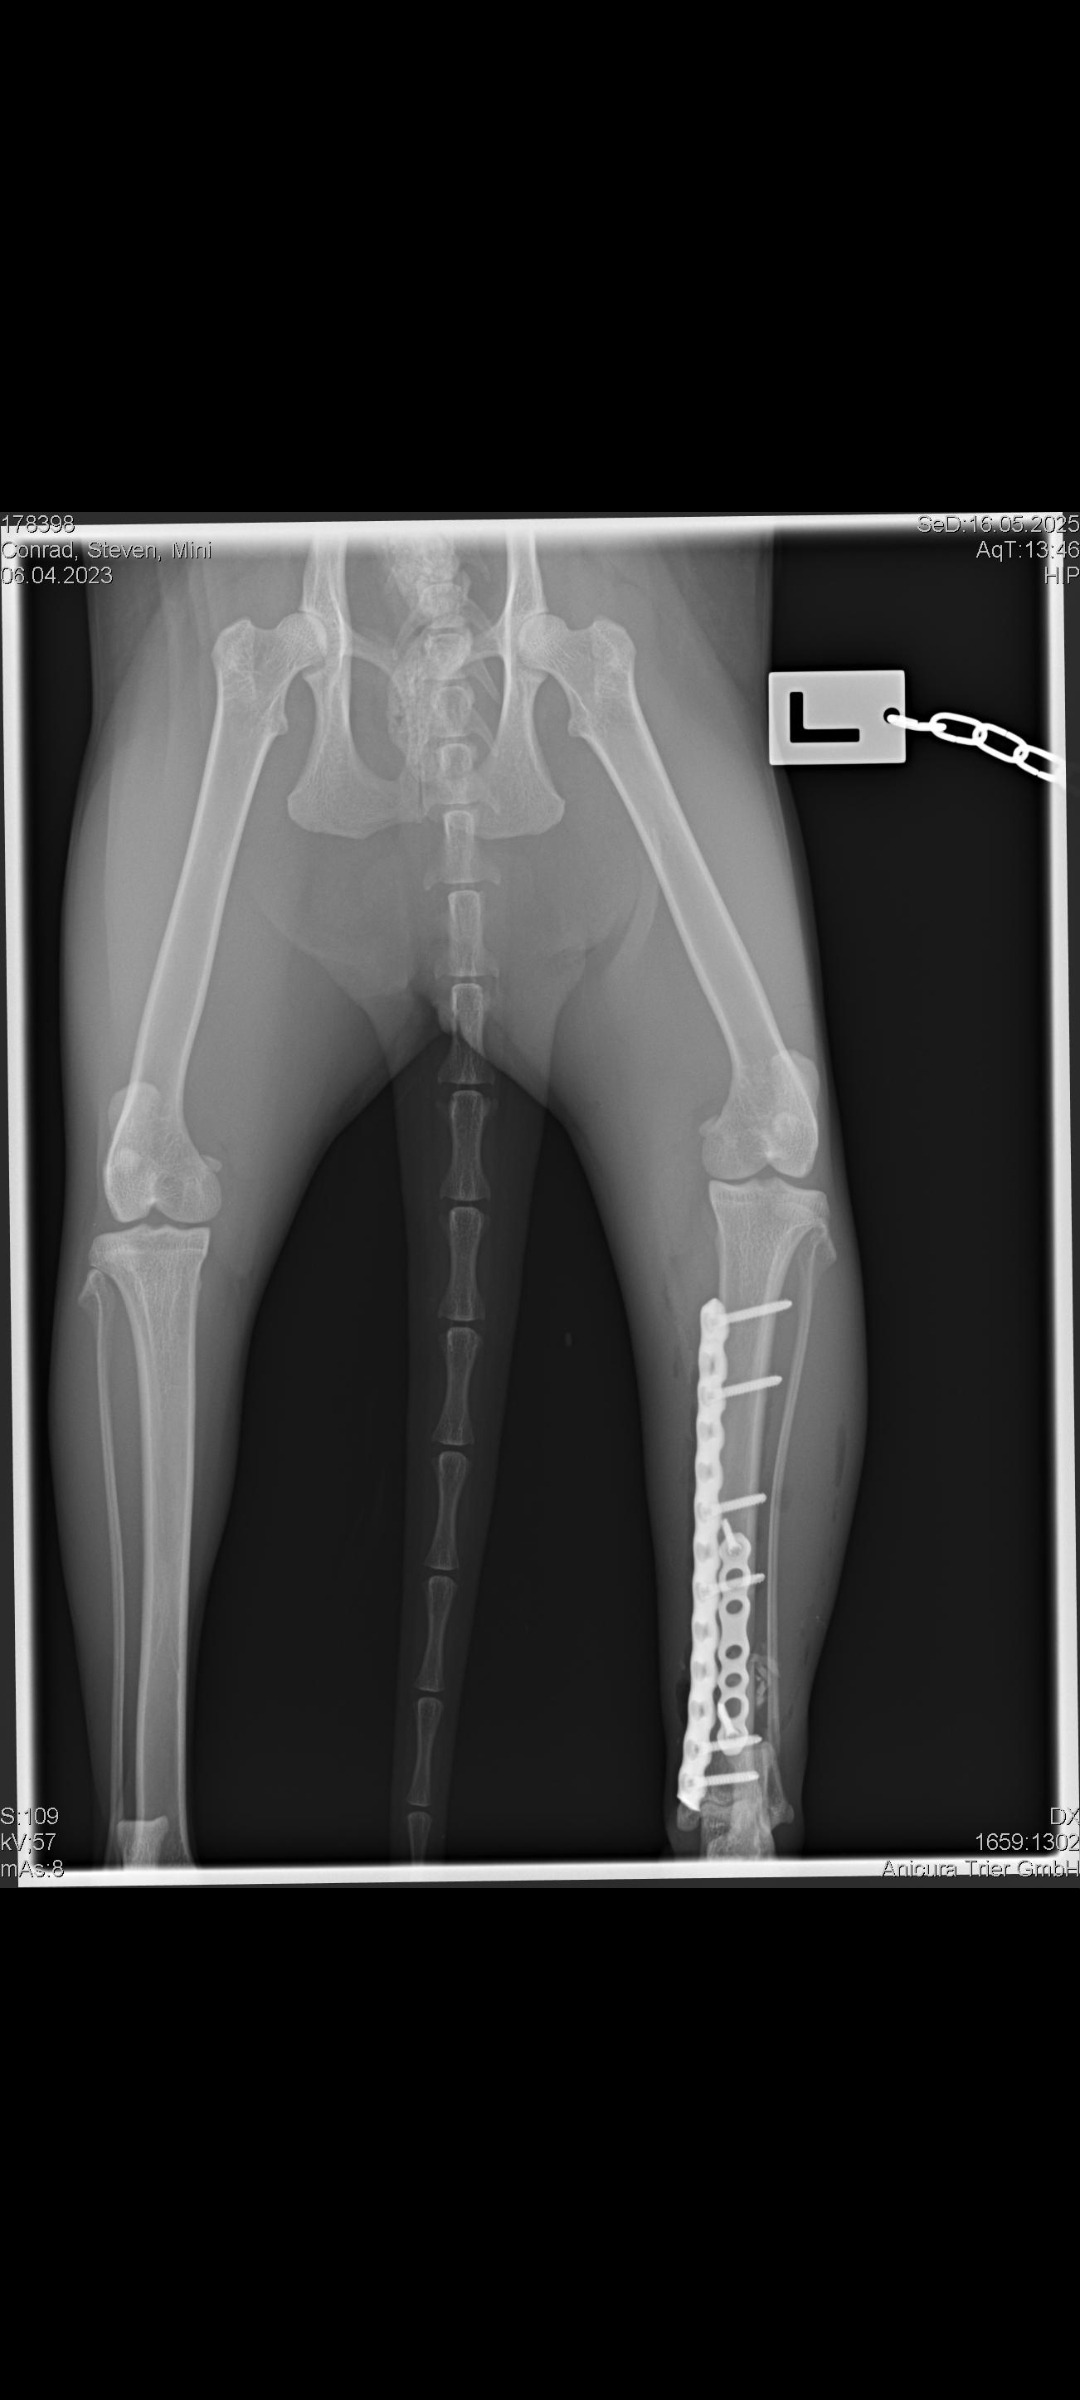

Am 16. Mai 2025 musste Mini aufgrund einer schweren Verletzung am Sprunggelenk operiert werden. Die Operation war aufwendig – es wurde eine Metallplatte eingesetzt, und sie musste anschließend acht Wochen lang in strikter Boxenruhe verbringen.

Kontrollröntgen, um zu prüfen, ob alles korrekt verheilt ist